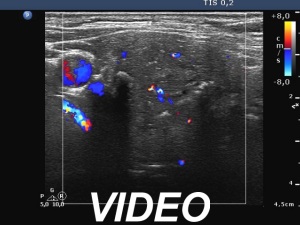

Ultrasonography. The thyroid was echonormal. A large hypoechoic nodule occupied almost the entire right lobe. The nodule showed various intranodular echogenic figures, including microcalcifications, macrocalcification and non-specific figures. The borders were indistinctive. The lesion was suspicious spreading extrathyroidal.